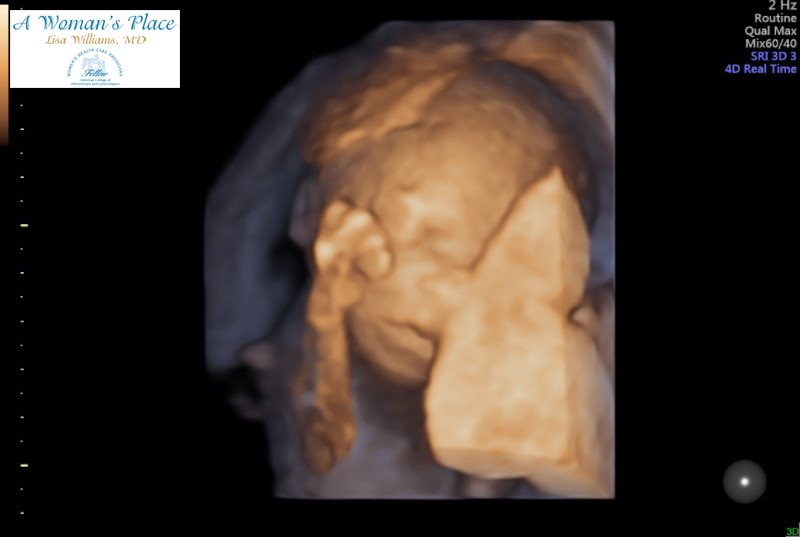

We had our anatomy scan this morning. Turns out baby number three is a boy! Couldn’t be more excited! We got so many great pics but I love this one. It looks a little creepy but when she was trying to get this picture the baby kept opening his mouth and sticking his little tongue out at us. You can even see his tongue in the pic. It was so cute and funny. I already love him so much!!